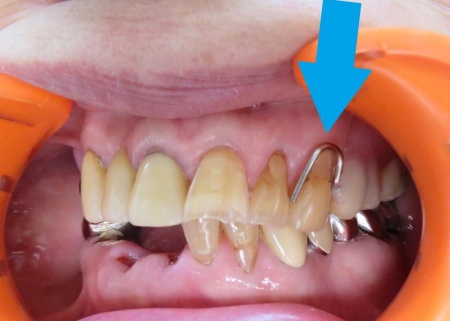

拝見したところ、左上前歯にかかっていた金属バネ(クラスプ)が折れており、入れ歯をしっかりと固定することができなくなっていました。

クラスプが折れたままでは、入れ歯の安定性が低下して外れやすくなる、残っている歯や歯茎に負担がかかる、食べ物を噛んだり会話をしたりすることが難しくなるなどのリスクがあります。